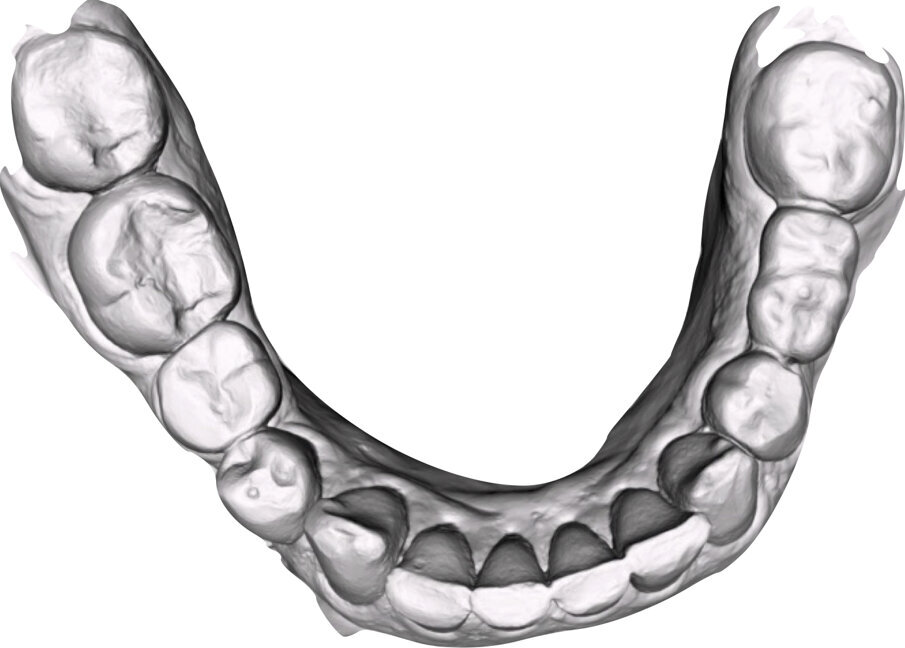

Si esegue perciò cefalometria (Fig. 8) su radiografia latero-laterale (Fig. 9) e axiografia dei movimenti limite (Cadiax Compact, Gamma Dental) (Fig. 10) per la programmazione di un articolatore a valori medi (Artex TR, AmmanGirrbach) e montaggio dei modelli con arco faciale, che confortano nella produzione di un primo provvisorio prelimatura con rialzo arbitrario della VDO di 5 mm sull’asta incisale e miglioramento di OB e OJ, a scopo pre-terapeutico interlocutorio e di immediata risoluzione estetica. Conclusa la necessaria terapia causale e restaurativa viene eseguita la scansione intraorale delle arcate (TRIOS 3 Pod, 3Shape) (Figg. 11-14) e del rapporto articolare con cera di RP (Fig. 15). La scansione è stampata (VisiJet RWT, 3D Systems) con monconi sfilabili tramite stampante 3D (ProJet MJP 2500 Plus, Selltek) (Figg. 16-20), i modelli derivanti sono zoccolati e montati con cere di RP e arco faciale su articolatore a valori individuali (Reference SL, Gamma Dental). La programmazione dell’articolatore derivante dalla registrazione axiografica è ora eseguita come da indicazioni del software (Gamma Dental software, sia per l’uso degli inserti condilari ed incisali, sia per la definizione degli angoli di SCI e di Bennet (Fig. 21). Lo spazio protesico risultante a una VDO adeguata alla riabilitazione dei denti anteriori vitali, con anatomia non ulteriormente modificabile, è insufficiente per uno stabile ripristino dei rapporti occlusali, specie nei tragitti funzionali. Si decide perciò di impiegare due inserti rossi di programmazione di protrusiva (+2 mm) per riposizionare la mandibola in TRP (Figg. 22, 23).

Ciò consente un miglioramento dei rapporti interarcata, un guadagno di spazio protesico in regioni premolari e molari, ed il mantenimento di uno spazio protesico conforme ad una corretta anatomia per i denti vitali da 1.3 a 2.3. Al paziente viene pertanto aggiornato il piano di trattamento e proposta la riabilitazione in TRP, con la previsione di overlays all’arcata inferiore per costruzione del nuovo piano occlusale. In posizione terapeutica sono modellati i coni delle centriche attive sui monconi sfilabili all’arcata inferiore, per la successiva individuazione al CAD con modulo articolatore del piano occlusale studiato. Questo rapporto articolare in TRP è ora scansito con scanner da laboratorio Xanos Evo Scan Compact (Fig. 24).

I modelli sono così importati in corretta posizione spaziale tramite il modulo exocad Virtual Articulator (Fig. 25). Non avendo a disposizione nel CAD l’analogo virtuale dell’articolatore Reference SL, viene impostato il sistema virtuale SAM, che usa lo stesso piano di riferimento axio-orbitale e geometria sovrapponibile al Reference SL. Per la programmazione virtuale dei parametri funzionali dell’articolatore si riesegue l’output dall’axiografia elettronica con Gamma Dental per SAM (Fig. 26). Si procede perciò ora con la modellazione CAD della ceratura mantenendo il riferimento dato dal piano occlusale individuato dai coni di centrica scansiti con l’articolatore (Fig. 27). L’articolatore virtuale consente una prima verifica dei rapporti occlusali tra gli elementi e un abbozzo di funzionalizzazione delle cuspidi con strumenti virtuali dinamici, che permette di arrivare ad un CAD design vicino alla morfologia ricercata (Figg. 28-33). Il modellato è ora fresato in cera Yeti Dental al CAM con fresatore VHF Cam5-S1 ed i denti in cera, tutti singolarmente sfilabili, sono posizionati sui modelli eseguiti con stampa 3D.